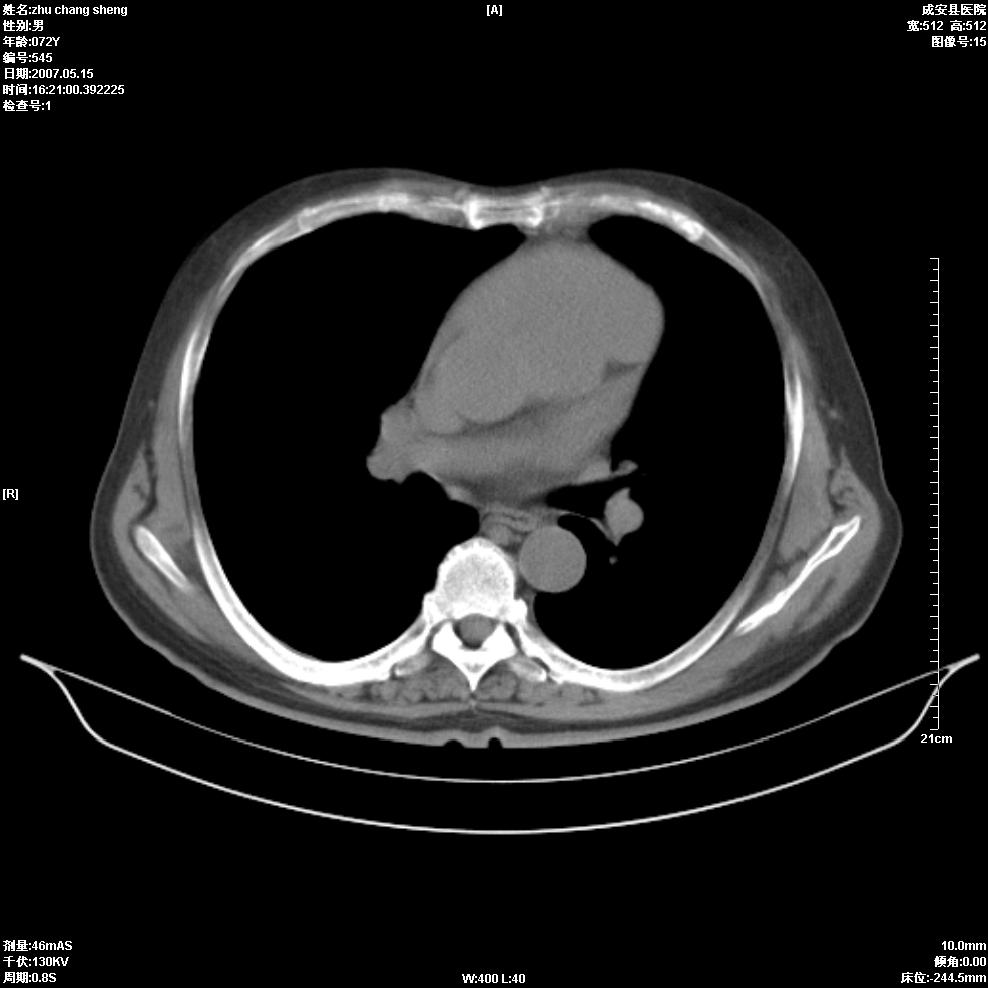

以下是引用医博云天在2007-5-15 19:10:00的发言:[br]心包积液,胸腔积液,心影增大,左心为主。

以下是引用zhangzhongshou在2007-5-15 20:21:00的发言:[br]心包积液可以肯定有,肿块显示不清,建议增强或mri检查。

以下是引用jinning在2007-5-15 21:06:00的发言:[br]心包积液可以肯定,建议增强或mri检查吧!

以下是引用拾荒者在2007-5-15 22:28:00的发言:[br]心包膜增厚,有少量积液,右室前壁示均匀软组织密度影,边界欠清,建议增强扫描或mri检查与室壁瘤鉴别。

以下是引用还珠格格在2007-5-19 9:50:00的发言:[br]病人与5月18日 做了核磁增强扫描 确诊为前上纵隔侵袭性胸腺瘤。